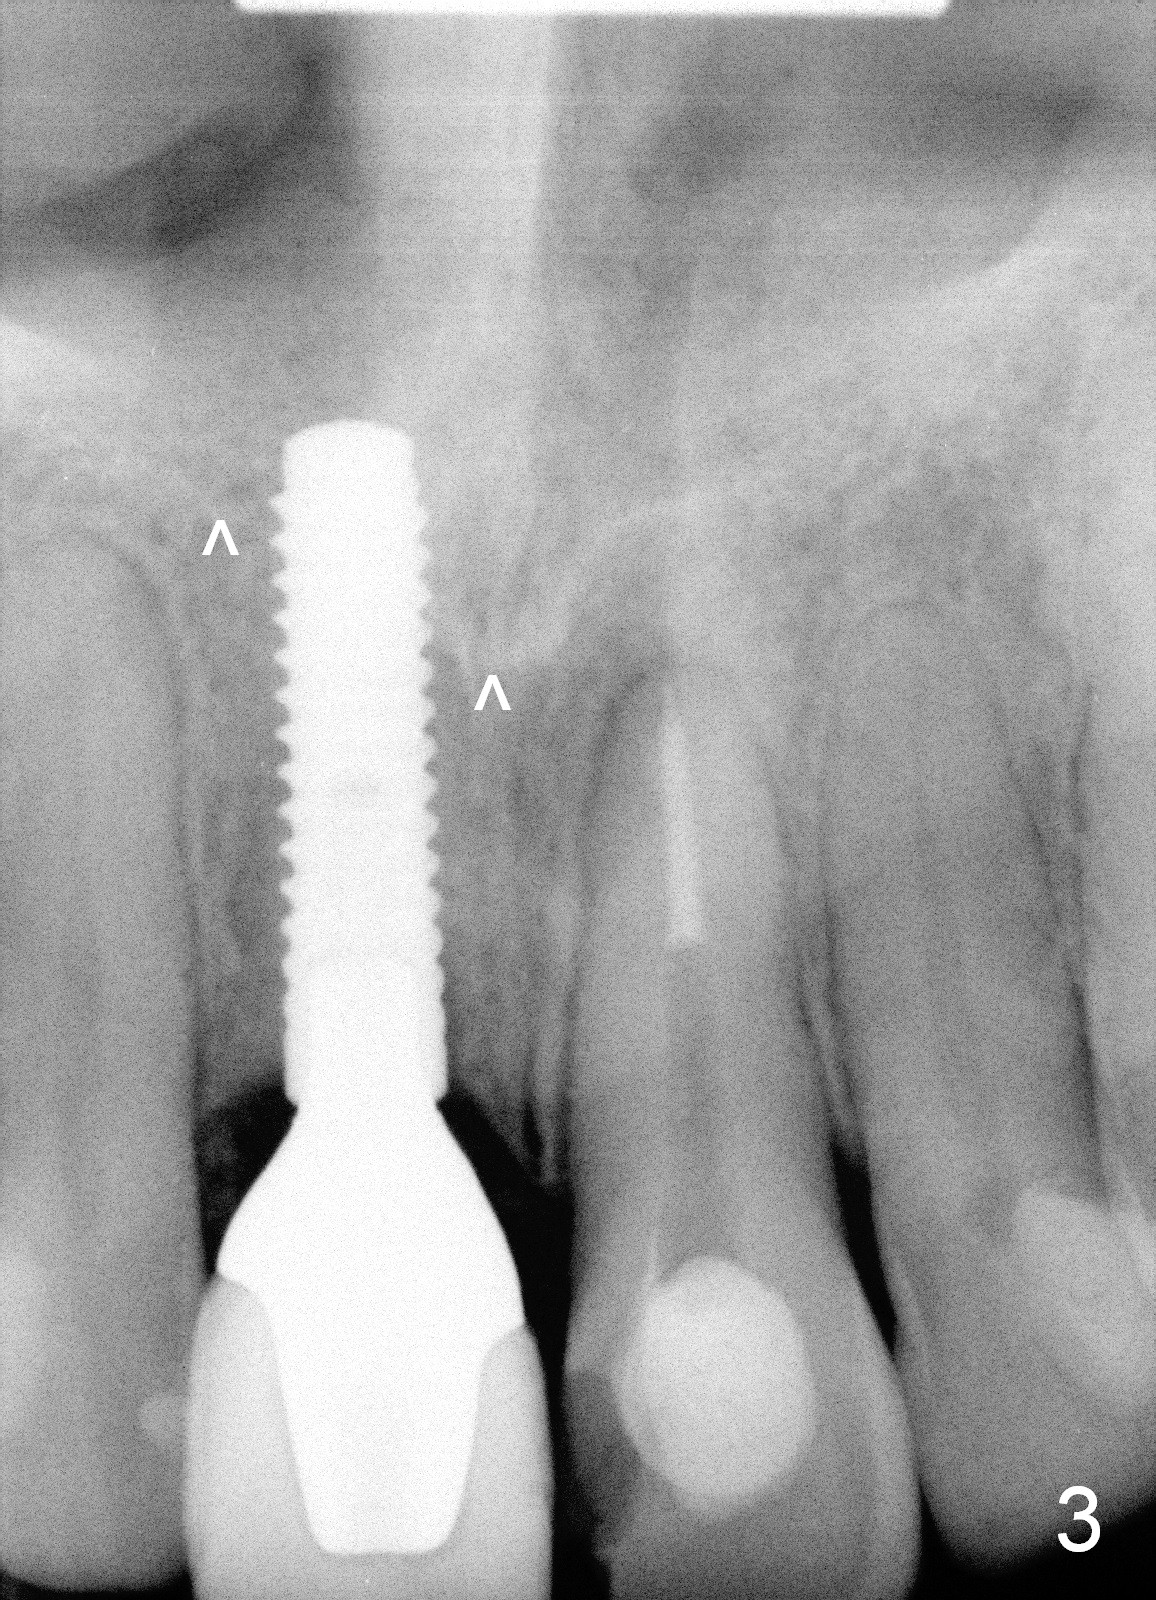

In contrast, delayed implant is most likely associated with mal-positioning in 3 D, including invasion of the nasal floor (Fig.3) due to bone loss. When segemental osteotomy is needed, the transverse cut is difficult (Fig.4). The implant bone segment may be not stable once moved (Fig.5), since no block graft can be inserted, not to mention trauma and hemorrhage in the nasal floor. The segment may relapse (Fig.6).